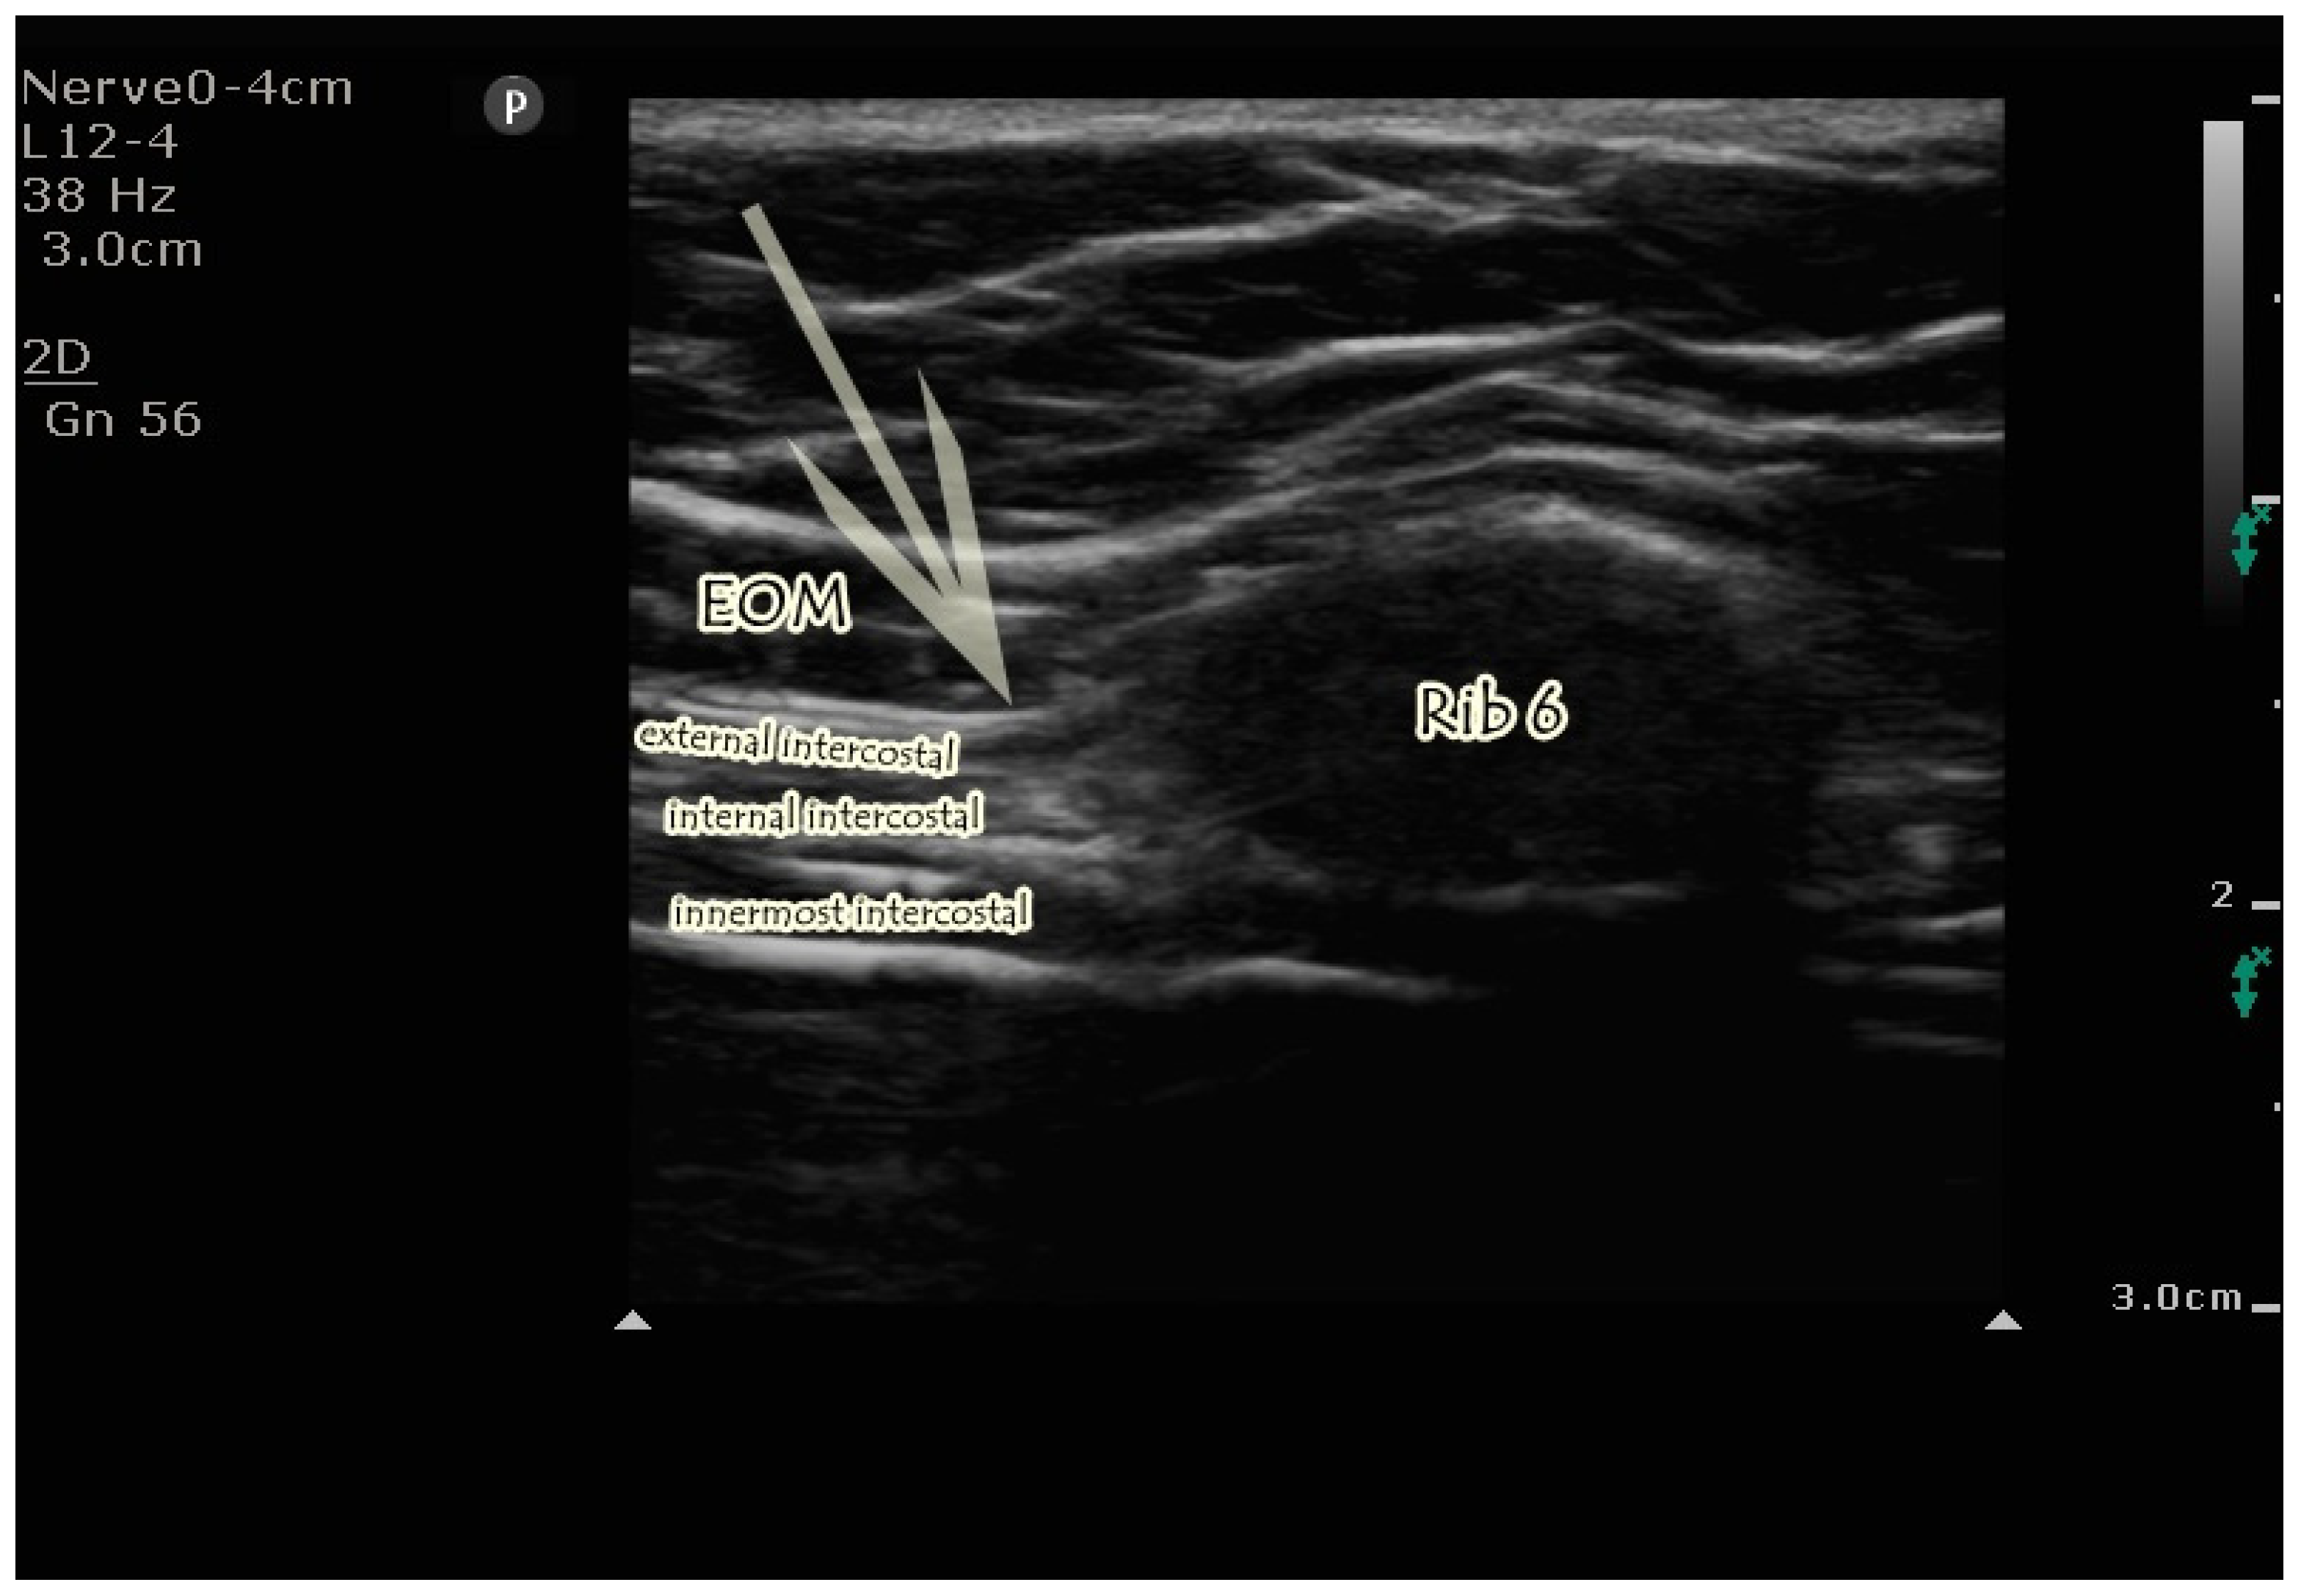

2.4.2. US-Guided EOIB